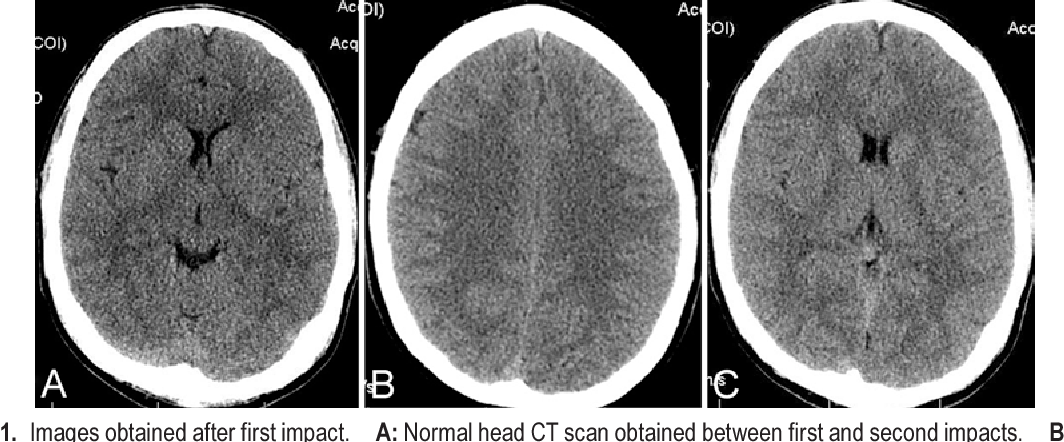

Second impact syndrome [SIS] refers to second concussion following primary brain injury. Getting a concussion after primary brain injury is fatal as it can cause death within 2-5 minutes. The cause of death is inability of the brain to autoregulate condition following the second injury. Hence, rapid edema ensues and death occurs. This is the reason why players after getting a concussion are not allowed to return to the field since second injury would cause rapid death. Reference: https://www.ncbi.nlm.nih.gov/pmc/articles/PMC2672291/ Image via: https://www.semanticscholar.org/paper/Second-impact-syndrome-in-football%3A-new-imaging-and-Weinstein-Turner/69a9d6c9338d3c02dfff866d65b71af65c0e8253